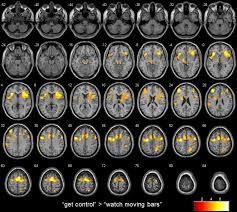

Por ejemplo, se puede solicitar a la persona mover su mano durante un tiempo, la región cerebral que tiene participación en el movimiento de la mano presentará vasodilatación, y ocasionará que cambie la concentración de desoxihemoglobina de la zona. Esto provoca un cambio del magnetismo local, detectado por el resonador. El área que presentó el cambio se puede observar como una zona de color sobre el fondo de grises de la resonancia (como se muestra en las imágenes).

Los investigadores Levesque,  Beauregard y Mensour. (2006) trabajaron con dos grupos de niños con Trastorno por Déficit de Atención con Hiperactividad (TDAH); la mitad formó un grupo control (CON) y la otra mitad el experimental (EXP). Realizaron a ambos grupos, al iniciar el estudio, una RMF (TIME 1), haciendo dos tareas (Stroop y No-Go minus Go) que evalúan el autocontrol y la atención. Solamente el grupo EXP entrenó con neurofeedback, mientras que el CON estaba en lista de espera. Después de 20 sesiones de entrenamiento repitieron a ambos grupos la RMF (TIME 2), junto con las dos tareas antes mencionadas (ver imágenes de este y el siguiente párrafo).

La primera RMF reveló activación en la zona parietal en ambos grupos en ambas tareas. Mientras que la segunda RMF, reveló solamente en el EXP activación adicional en zonas subcorticales, prefrontales y del giro del cíngulo. Todas esas zonas están relacionadas con autocontrol de la conducta, regulación de la atención y de las emociones.

Este estudio demostró por primera vez que el neurofeedback provoca cambios reales en el cerebro, los cuales están relacionados a los cambios cognitivos y conductuales de los clientes.

Fig. 3. Imagenes de la RMF de dos grupos, uno control y otro de niños con TDAH antes y después de entrenar con neurofeedback (sólo este último grupo).

Fig. 4. Imágen de RMF del grupo con TDAH después de entrenar con neurofeedback, al hacer una tarea que impica inhibición de la conducta.